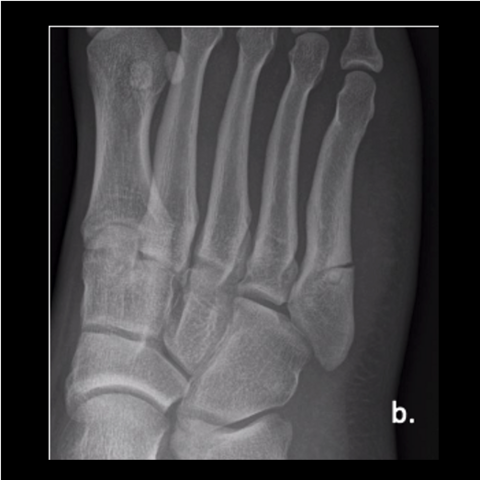

Figure 1b

Figure 1b. A 23-year-old male trainee twisted his foot while running, presenting a week or 2 later. Here is an injury film.